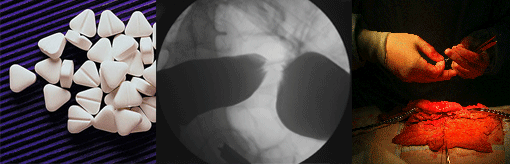

Bowel Cancer - Colonoscopy

Colorectal cancer is 3rd most common cancer overall. It is the second most common in women after breast cancer. It is the 2nd most common cause of cancer death in the UK. It affects about 1 in 20 people in the UK.

Bowel cancer screening reduces the risk of dying from bowel cancer by 16% (see more). At we offer colonoscopy (camera) for those at risk, persistent symptoms like bleeding, or those with family history or those that have reached the age of 60. We offer this to patients with insurance or who are self-paying.

Haemorrhoidal pain - A thing of the past

The days of prolonged post-operative pain after haemorrhoid surgery is over for most patients.

With the new minimally invasive haemorrhoidal artery ligation operation (HALO) or transanal haemorrhoidal dearterisation (THD), the surgical treatment is now essentially painless. Sitting is no longer a problem and you can resume normal activity in 24-48 hours.